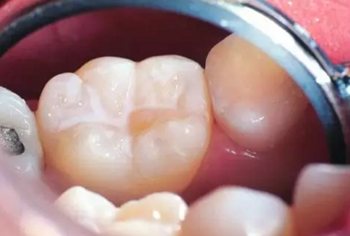

因為我們的牙齒表面并不是完全平滑的,存在很多溝隙,尤其是后面的磨牙,表面的窩溝縫隙尤其深和復雜。在刷牙的時候,牙刷的刷毛是很難進入這些窩溝進行清潔的,因而這些窩溝深處容易殘留食物殘渣,就導致了蛀牙的發(fā)生。

牙齒窩溝處成為蛀牙高發(fā)地,因此,對于剛萌出、尚未齲壞的牙齒來說,將這些窩溝封閉起來,是最好的預防蛀牙的方法。

窩溝封閉的原理很簡單,就是用一種對人體無害的高分子樹脂材料把窩溝填平,待樹脂硬固后可以長期保留在窩溝中。這就好比給牙齒穿了一層保護衣,保護牙釉質(zhì)不受細菌及代謝產(chǎn)物侵蝕,從而預防齲齒的發(fā)生。

只要有窩溝裂隙比較深的牙齒都可以做窩溝封閉,而窩溝裂隙深的牙齒通常是磨牙。